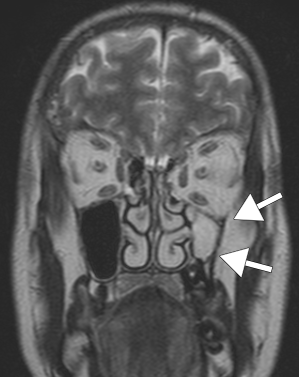

Рис. 2. Т2 - ВИ в корональной плоскости. Внутренняя стенка левой верхнечелюстной пазухи и крючковидный отросток смещены латерально; опущение дна левой глазницы.